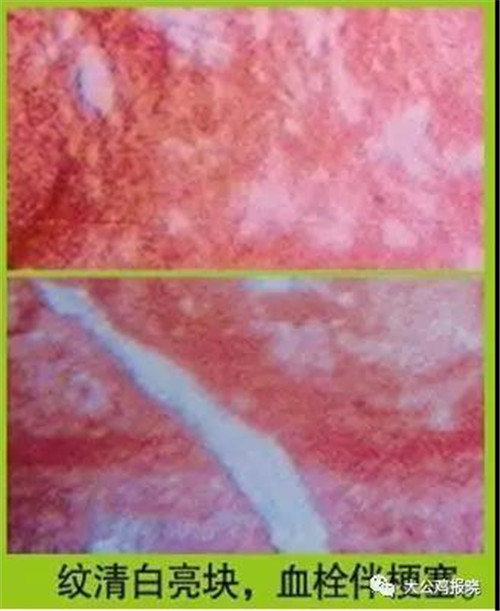

图3:微血管呈现纹清白亮块,分别可导致脑梗、肺梗、心绞痛、胃胀、腰痛、骨质增生。